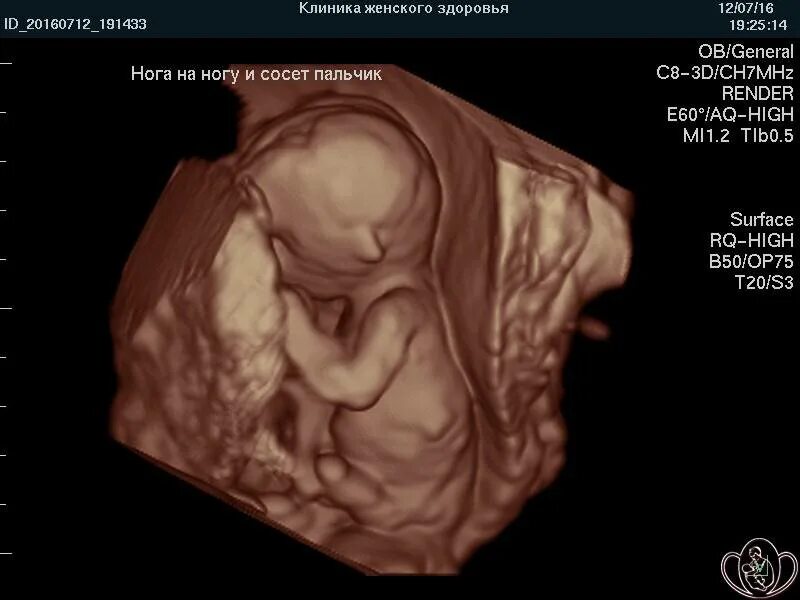

16 недель ощущения форум